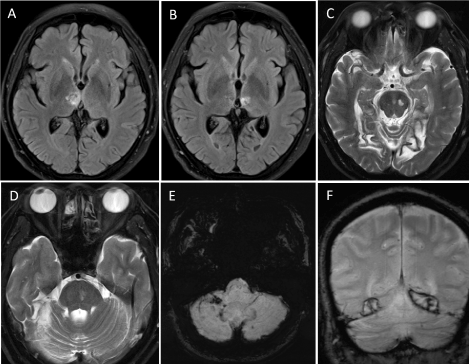

All previous imaging studies were reviewed and found that multiple recent infarctions had occurred on several areas in different time during period of 3 years. These infarcts involved bilateral thalami, midbrain, pons, left cerebellum, and bilateral medial temporo-occipital lobes. In our institute, MRI of the brain obtained 3 years after initial onset revealed multiple old infarctions in bilateral thalami, bilateral cerebellum, brainstem, and bilateral temporo-occipital lobes. There were encephalomalacic changes of bilateral occipital lobes. Susceptibility weighted imaging (SWI) and T2*-weighted gradient-recalled echo (GRE) image demonstrated evidence of old hemorrhagic transformations (Figure 2). Maximum intensity projection from 3D time-of-flight MRA of the cervical spine also showed an abnormal tubular-like lesion projected from posterolateral aspect of the right V3 segment between the level of C1 and C2. Also, there were irregularity and tortuosity of bilateral V1 and V2 segments (Figure 3A). The digital subtraction angiography (DSA) was further investigated and demonstrated the right VVAVF located at the level of C1-2 and drained directly into deep cervical veins (Figure 3B and 3C).

Figure 3. Anteroposterior view of maximum intensity projection from 3D time-of-flight magnetic resonance angiography of the neck (A) shows an abnormal tubular-like lesion projected from posterolateral aspect of the right V3 segment. There are irregularity and tortuosity of bilateral V1 and V2 segments. Anteroposterior (B) and lateral (C) views of the right vertebral artery injection demonstrate vertebro-vertebral arteriovenous fistula at the level of C1-2, draining early into deep cervical veins.